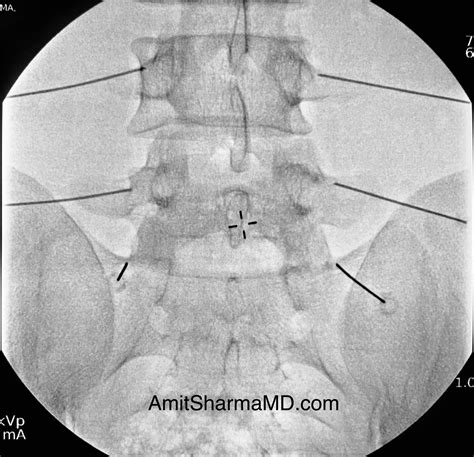

2. Guidance: Using fluoroscopy (live X-ray), the physician guides a needle into the facet joint. This ensures precise placement and minimizes the risk of complications.